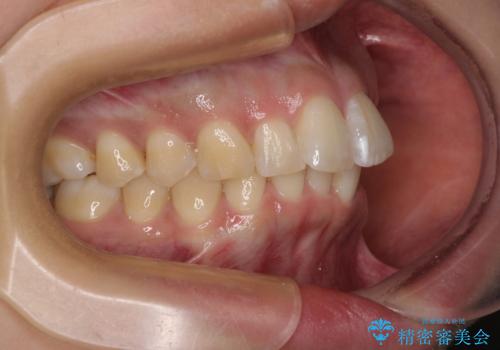

- 前方に主張した前歯2本を気にして来院された患者様です。

下顎前歯がデコボコしており、その影響で上顎前歯が前方に押し出されている状態でした。

口元が閉じにくいという印象はなかったため、非抜歯矯正にて歯列を整えていくこととしました。

上下左右の親知らずを抜歯し、上下ともに歯列を後方と側方に拡大し、口元を突出させることなくデコボコを解消することとしました。